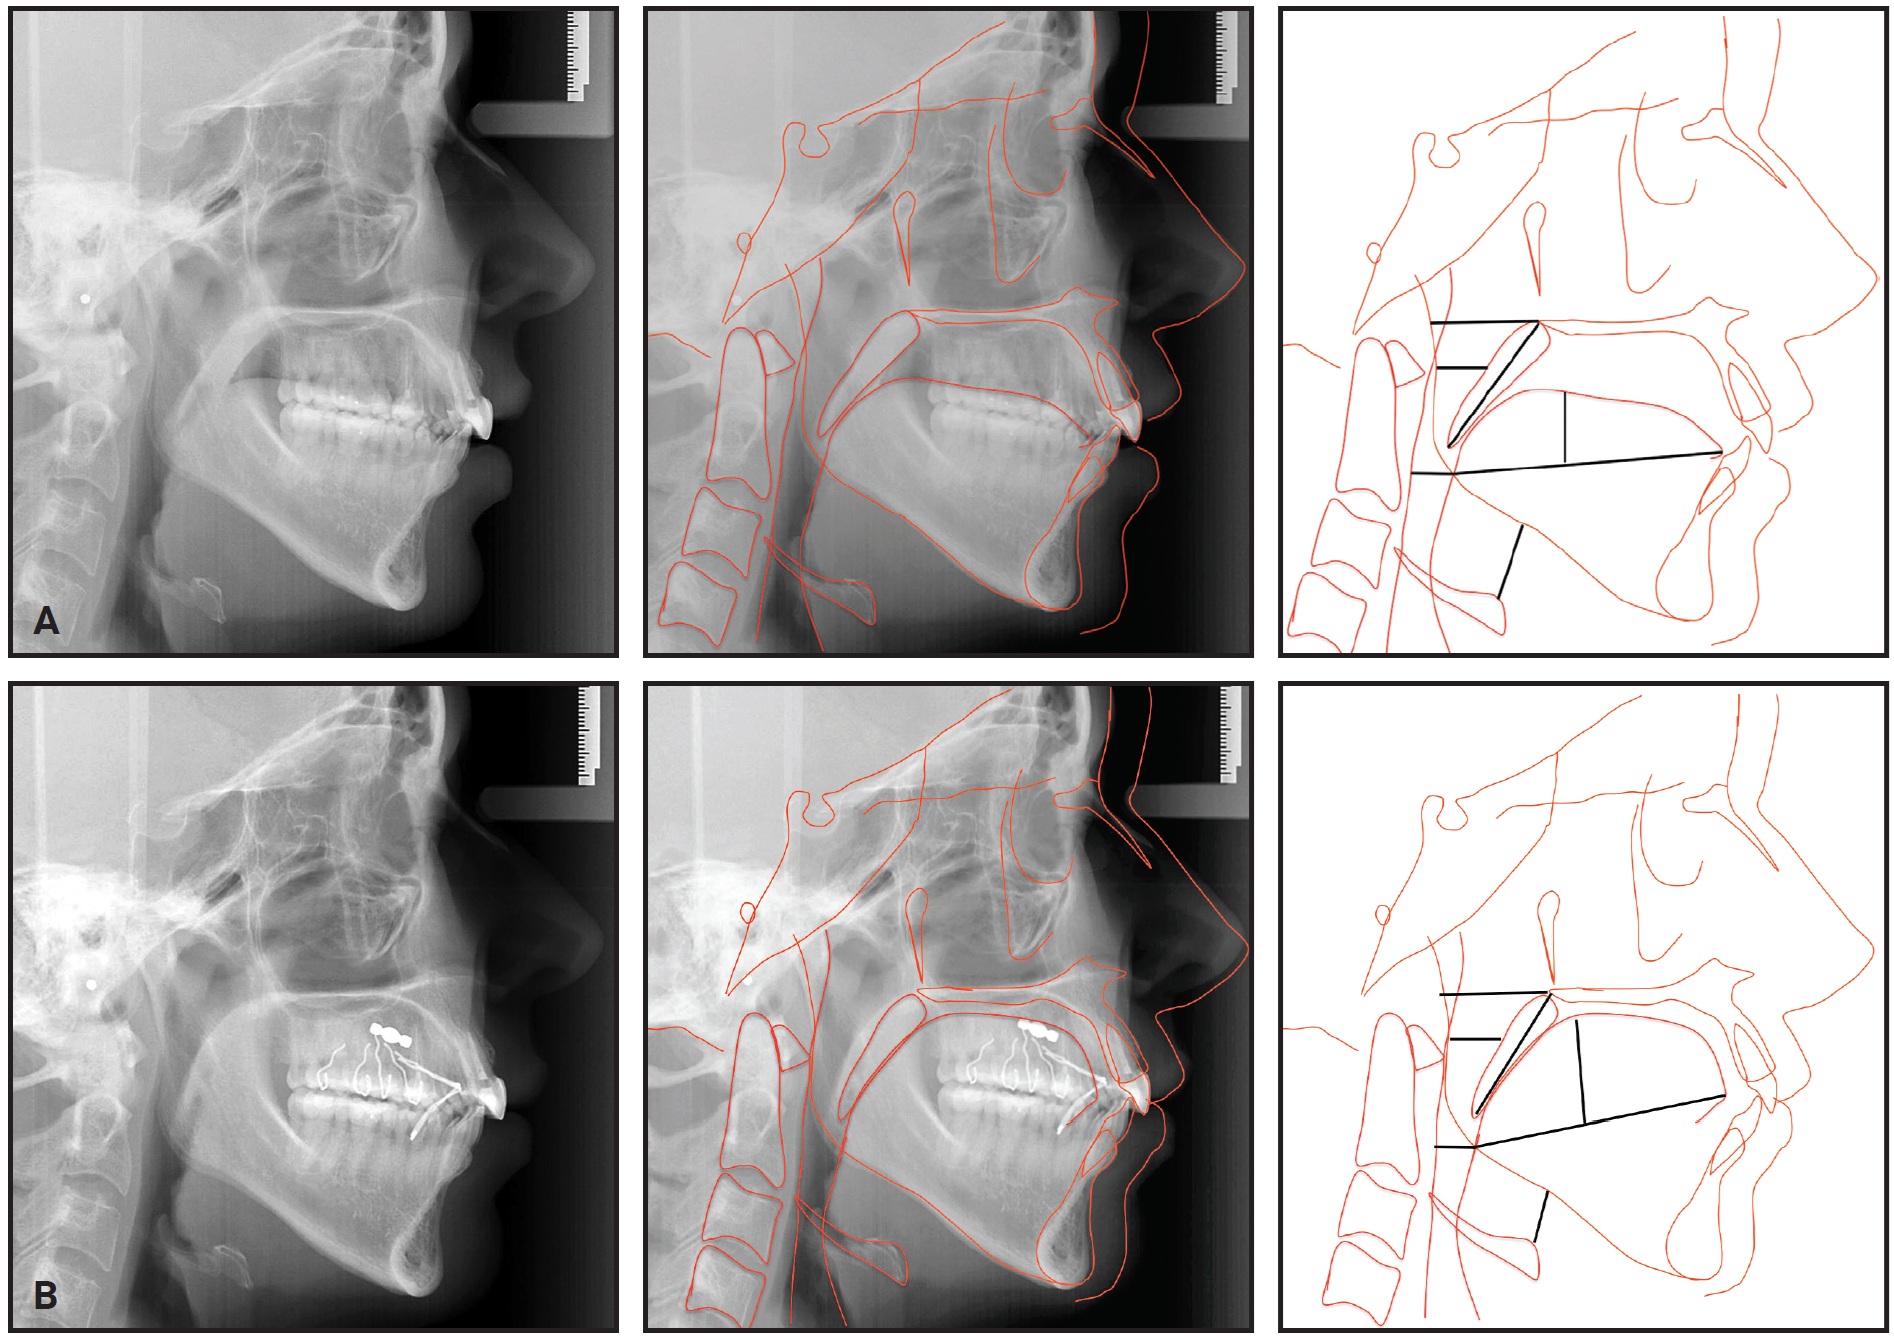

A 49-year-old male sought treatment to improve tooth positioning for subsequent prosthetic rehabilitation (Fig. 3).

Fig. 3 49-year-old male patient with skeletal Class III malocclusion and history of snoring and breathing cessation during sleep.

He complained of snoring problems and stoppages of breathing during sleep. Clinical examination indicated a dolichocephalic pattern with adequate lip seal and a skeletal Class III malocclusion due to maxillary retrusion. The patient had a Class III subdivision left canine relationship (Table 2), a distally rotated upper right first premolar, and a missing upper right second premolar, upper left first molar, lower left first premolar and first molar, and lower right first molar. The tongue volume was Class III, according to both the modified Mallampati and Friedman indices (Fig. 4).

Stainless steel MBT**-prescription brackets*** were bonded in both arches. The initial archwires were .014" nickel titanium, progressing to .016" nickel titanium and .018" stainless steel. After 12 months of treatment, the alignment had improved enough to start treatment with the Tongue Rehabilitator.

Rectangular .019" × .025" stainless steel archwires were inserted to improve the occlusion over the next 12 months. During this stage, implants were placed in the edentulous sites of the lower left first premolar and first molar (Fig. 5).

Fig. 5 After 20 months of treatment, including eight months with Tongue Rehabilitator.

Another six months later, after installation of the prosthetic crowns, the fixed appliances were removed.

A lingual 3-3 retainer was bonded in the lower arch, and a Hawley-type retainer was delivered for the upper arch. At bedtime, the Tongue Rehabilitator could be inserted into the telescopic tube of the retainer’s acrylic palatal plate. This approach fit well with the patient’s routine, since he worked with the public and his speech was affected when he was wearing the device.

Total orthodontic treatment time was 30 months (Fig. 6). At the three-month follow-up visit, we made slight adjustments to the retainer and Tongue Rehabilitator. The patient reported that his sleep quality had improved and he was waking up more refreshed, and that his wife also slept more comfortably.

Fig. 6 Patient after 30 months of treatment.